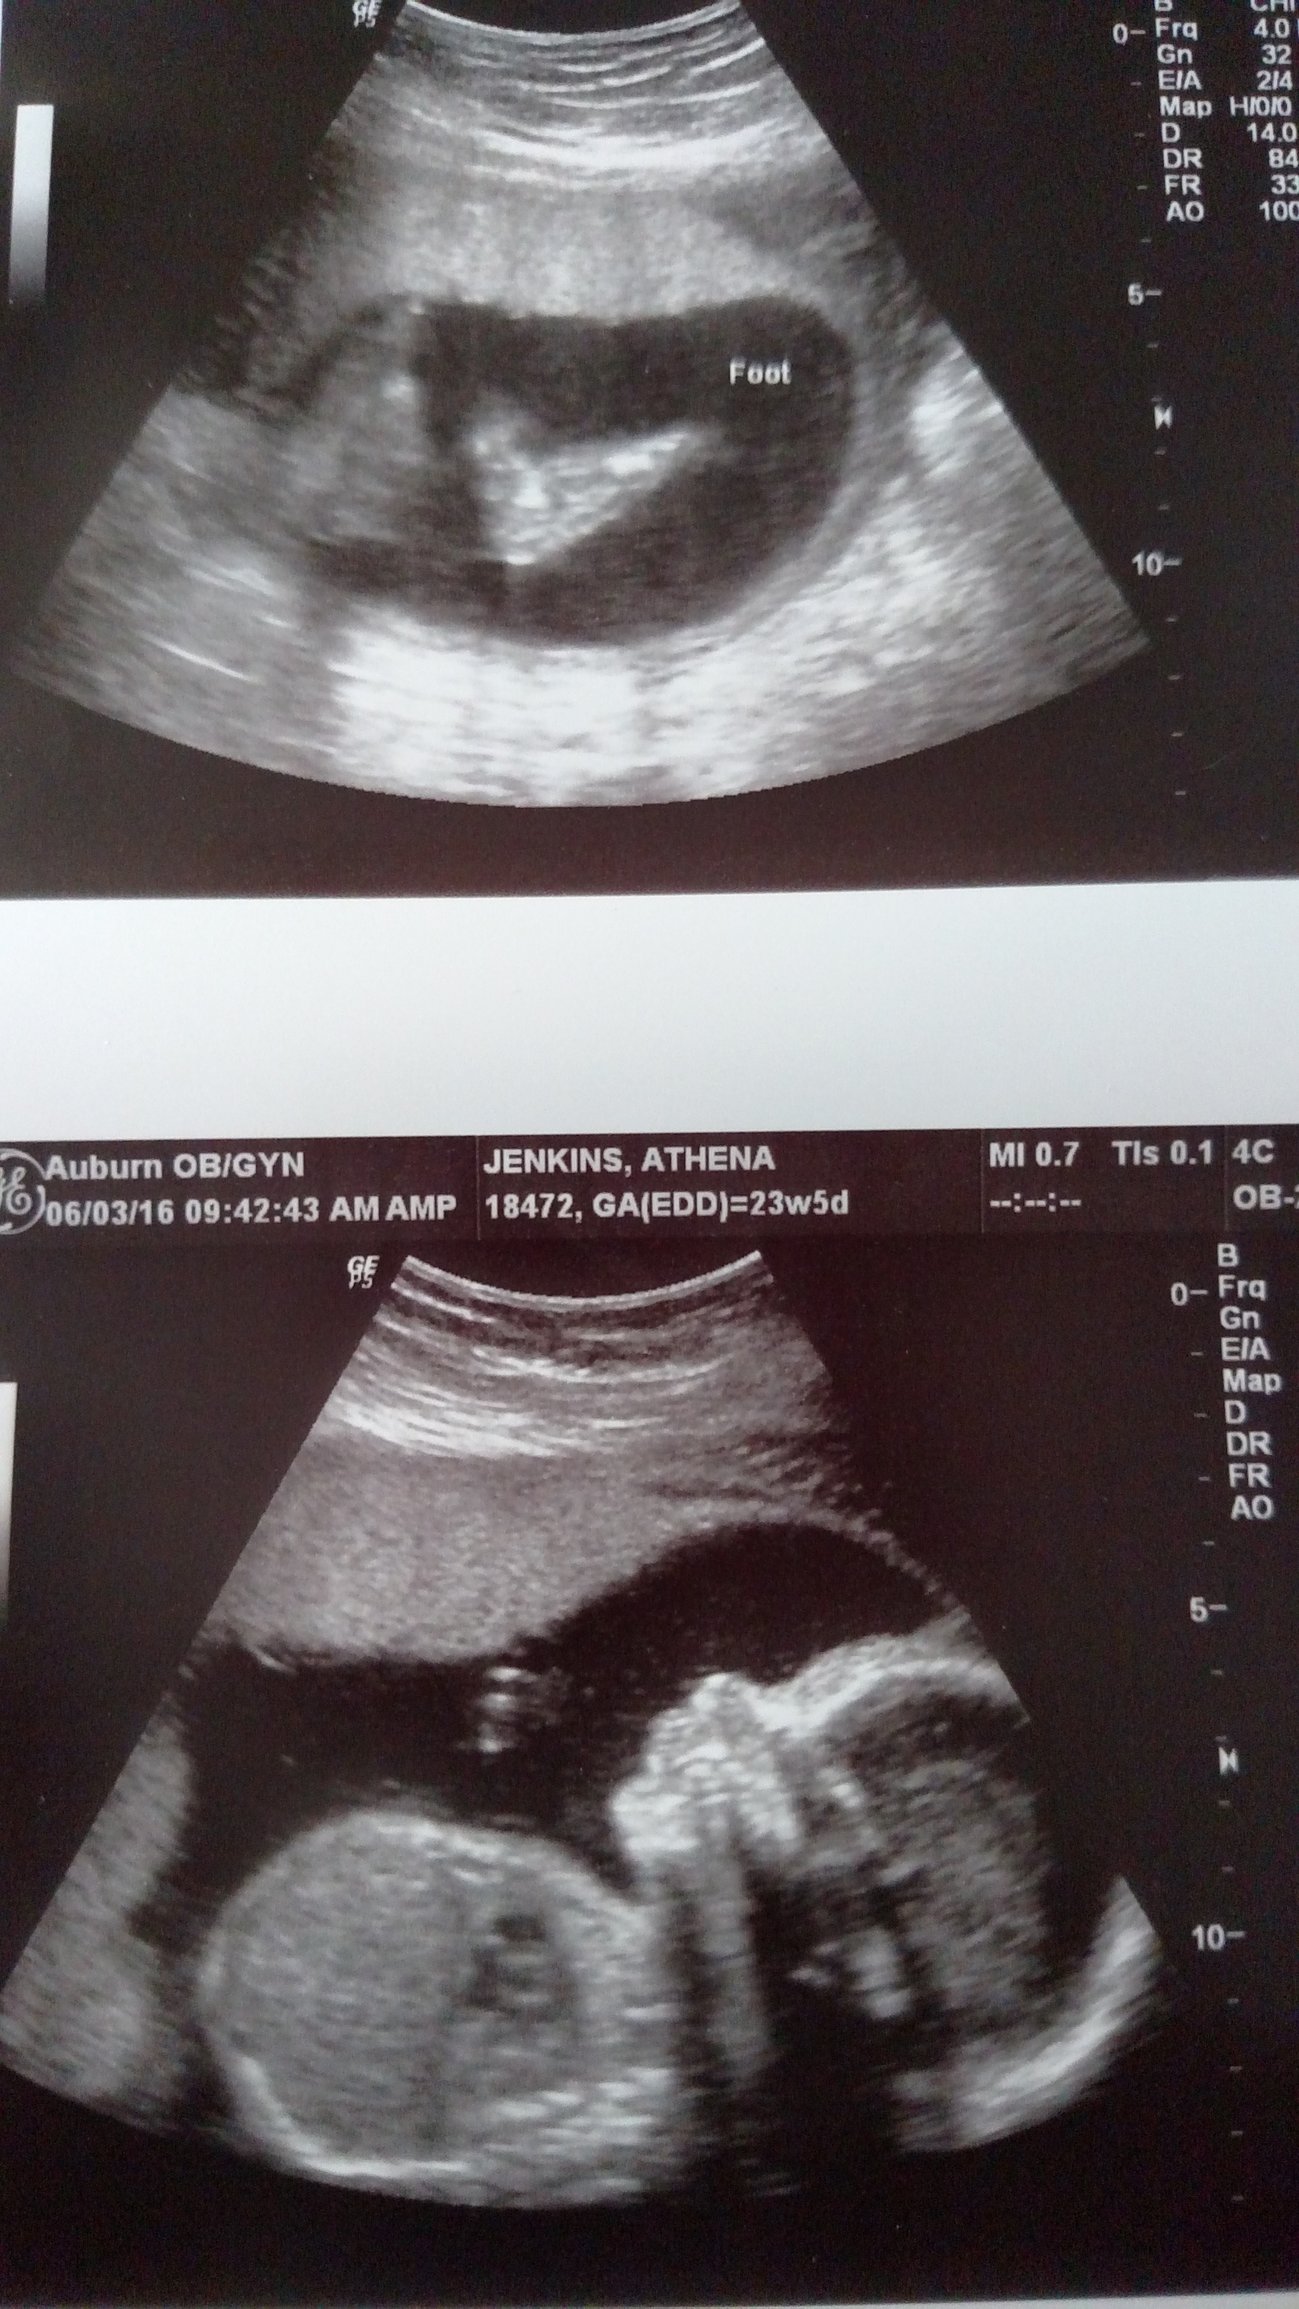

Can't believe I have a living breathing tiny human being inside of me! Baby was swallowing and putting hands on head. I also measured a week ahead! I also think I accidentally saw a penis when we are supposed to be team green! I am so excited!

Baby girl at 27.3. She kept her hands and feet in front of her face the whole time, we even saw her sucking on her toe. Can't wait to meet this little one!